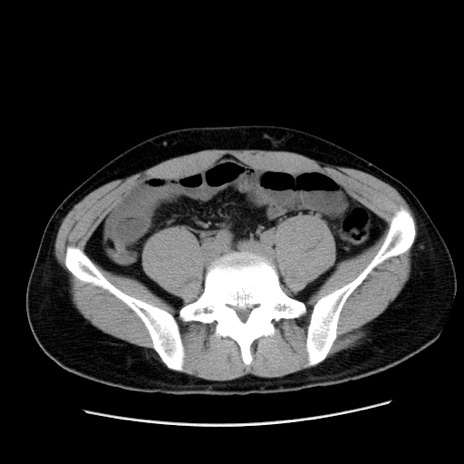

冠状断像